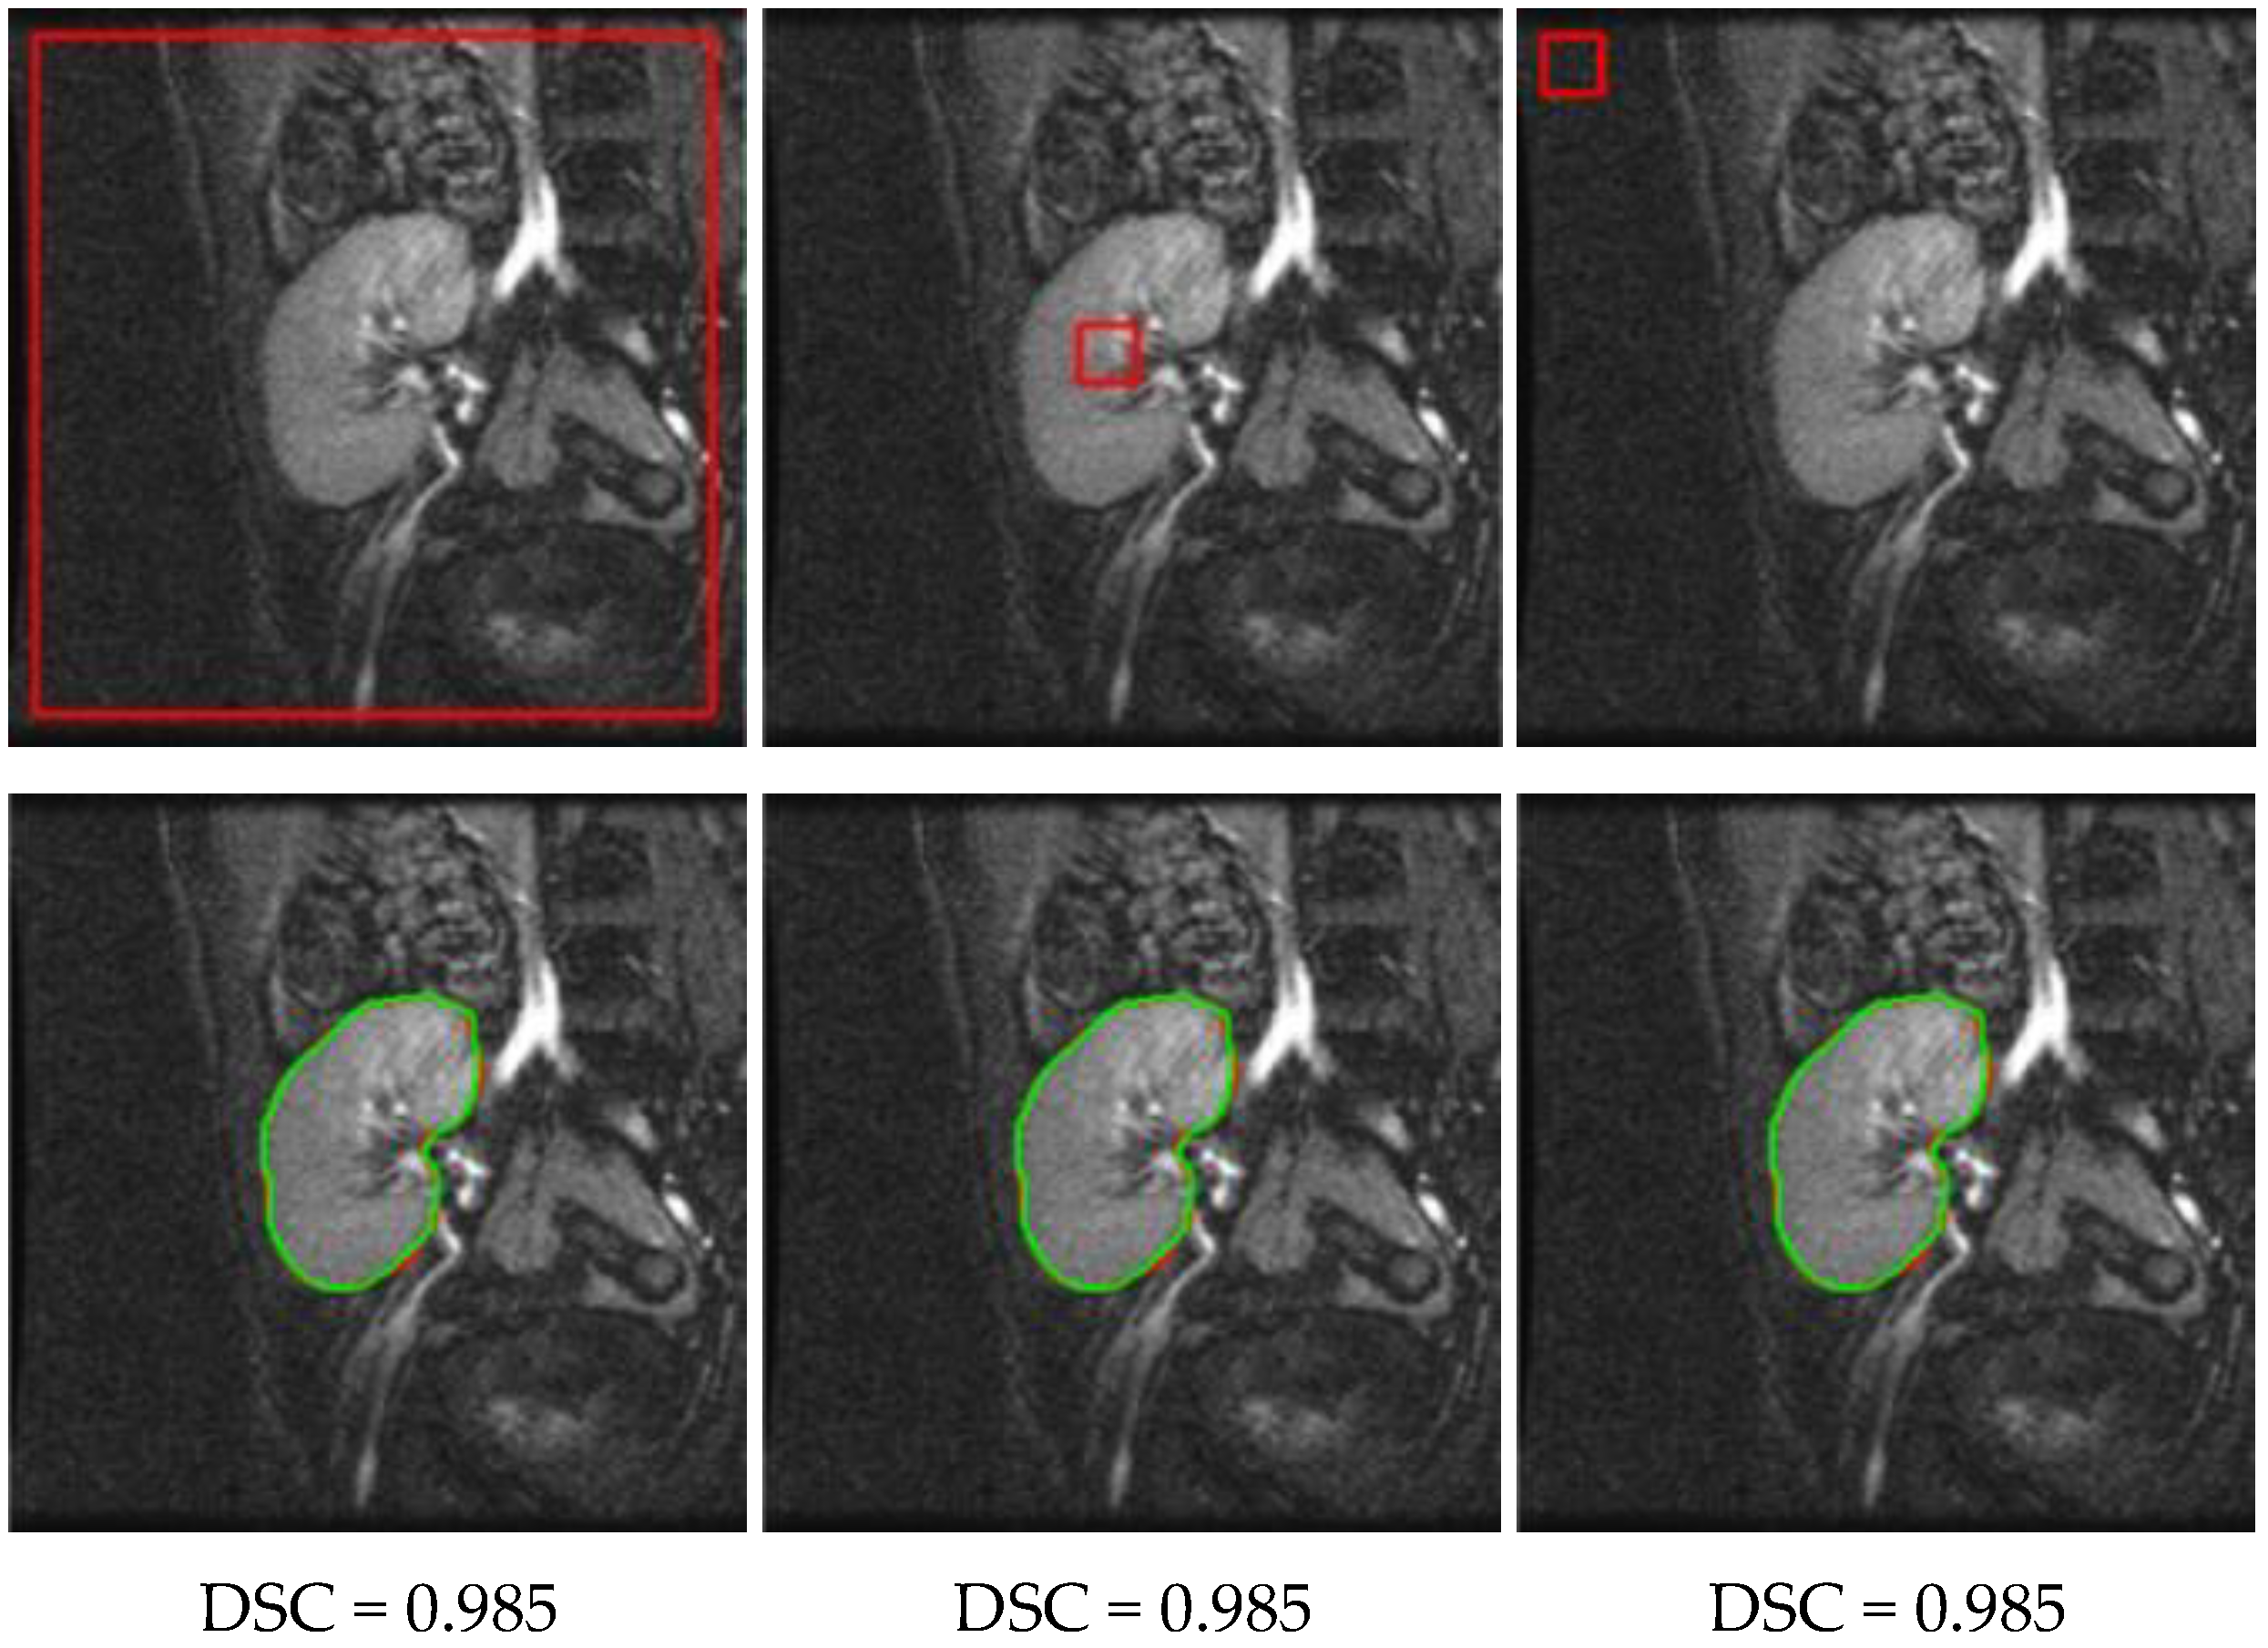

3.1. Method Performance with Comparisons to Other Methods

3.2. Ablation Experiments